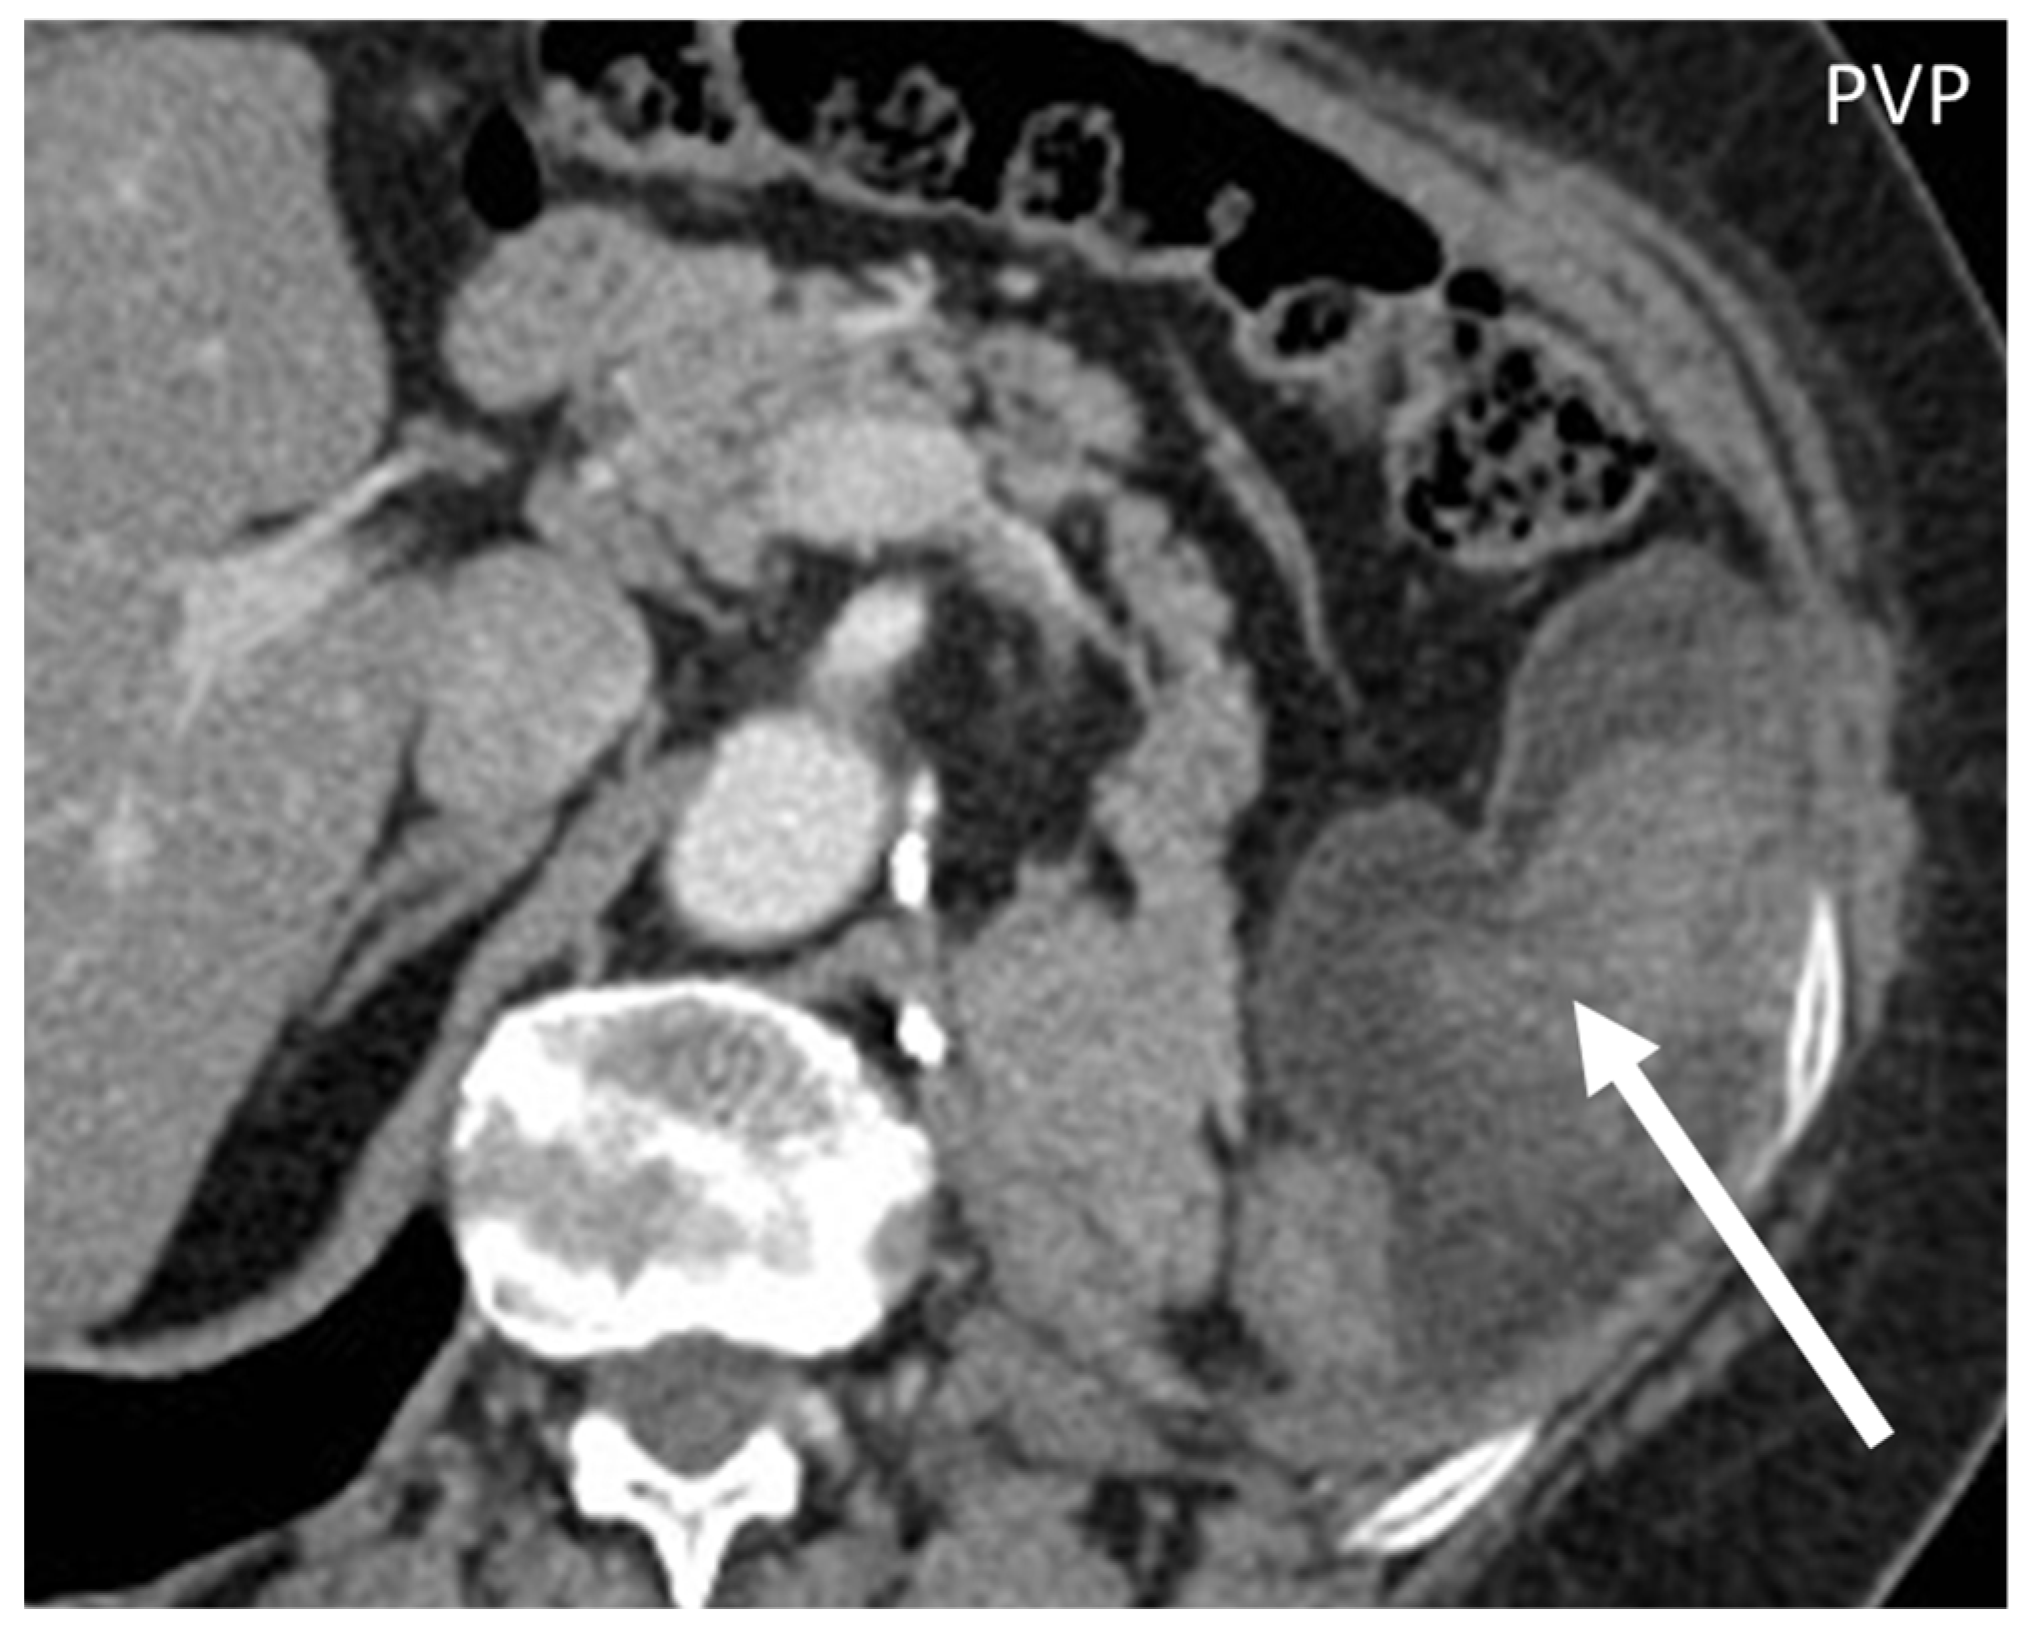

- Gastrointestinal Stromal Tumors (GIST): either primary (extraintestinal GIST, “EGIST”) [25,26] or secondary GIST of the abdominal wall are rare. When extended (>5 cm), GIST may have an aggressive behavior [25]. CT is the imaging modality of choice, showing heterogeneous vivid enhancement, and variable amount of necrosis. Peculiar findings include calcifications and cystic degeneration [27,28,29].

- Desmoplastic Small Round Cell Tumor (DSRCT): rare, highly aggressive sarcoma of adolescents, which primarily involves the serosal surfaces of the abdominal cavity infiltrating the abdominal wall [30,31,32]. Classic findings include bulky multiple, hypoattenuating, soft-tissue masses, with omental, serosal, and rectovesical involvement [31,32] and typical punctate or amorphous calcifications [32]. Modest heterogeneous enhancement is seen on arterial phase, without prolonged enhancement or portal washout [31,32] (Figure 10). On MR, DSRCTs are heterogeneously iso- to-hypointense on T1-w images, with hyperintense foci due to intratumoral hemorrhage [32].